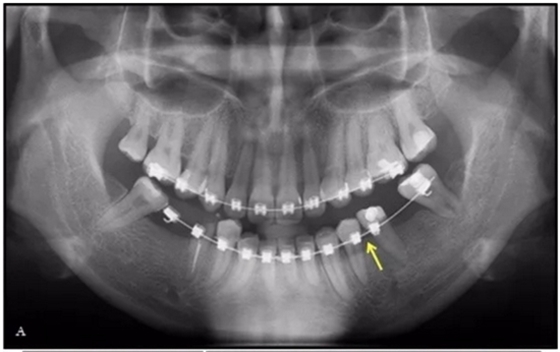

36歲;女性;尋求下頜左后方區(qū)域間隙管理的建議(圖1和圖2),通過治療獲得了良好的牙頜面效果(圖3和圖4)。她被診斷患有骨性I類和代償性牙性II類錯合畸形,并且上頜左側尖牙缺失(圖1和2)。大約七年前,由于不可修復的齲齒,拔除了下頜左側第一和第二磨牙(圖5)。37相鄰的第三磨牙向近中移動并傾斜入間隙,導致無牙頜間隙減小至約14 mm(圖2和圖5)。臨床和影像學評估顯示多發(fā)性齲損和在下頜右側567處有一不良的固定橋修復體(圖1和5)。此外,下頜左中切牙缺失,造成下頜中線向左側偏移約3 mm(圖1和圖2)?;颊咦栽V,她的右上第一前磨牙和左上尖牙在13歲時由其家庭牙醫(yī)拔除,因為它們被阻塞到頰側萌出(圖1)。上頜第二磨牙缺失(未知病因),并且相鄰的第三磨牙已經(jīng)轉移到第二磨牙間隙中。如補充材料所示,美國正畸學差異指數(shù)DI是28分。種植體部位(下頜左側和右側第一磨牙)由于復雜性得到額外4分(補充材料)。

完全固定的Damon Q設備(加利福尼亞州Glendora的Ormco)與制造商指定的弓絲和附件一起使用。下頜弓,一開始放入0.014英寸的鎳鈦弓絲,5個月后放入0.014×0.025英寸的鎳鈦弓絲。舌側扣和鏈圈放置在下頜尖牙和第二前磨牙上以控制扭轉。在治療的第7個月,將下頜弓絲換成0.017× 0.025英寸的β鈦絲。另一個舌側扣和鏈圈放置在下頜左側第三磨牙上以提供近中牽引力(圖9)。在16個月的治療結束時,所有的扭轉都得到了矯正,缺牙間隙縮小到8 mm(圖8),但由于頰側骨板的嚴重吸收,牙槽嵴的寬度仍然很窄(約3 mm)(圖9)。通過正畸移動下頜左側第二前磨牙,在前磨牙之間產(chǎn)生一個種植部位。在第一和第二前磨牙之間的弓絲上放置一個推簧,并將舌側扣和鏈圈放置在第一前磨牙和第三磨牙之間(圖9),在頰側和舌側施加力。施力均為輕力,每個表面上約2盎司(28.3 cN)以控制牙根側面的吸收。

圖10.經(jīng)過7個月后,以每月1毫米的速度牽引下頜左側第二前磨牙,正畸產(chǎn)生的種植部位長約7毫米。通過使用固定矯治器保持間隙6個月。根尖X線片顯示第二前磨僅有少量牙根遠中面吸收。

經(jīng)過32個月的活動治療后,上下牙弓排齊良好,下頜第一磨牙區(qū)的雙側牙間隙可用于種植(圖12,A和13,A)。